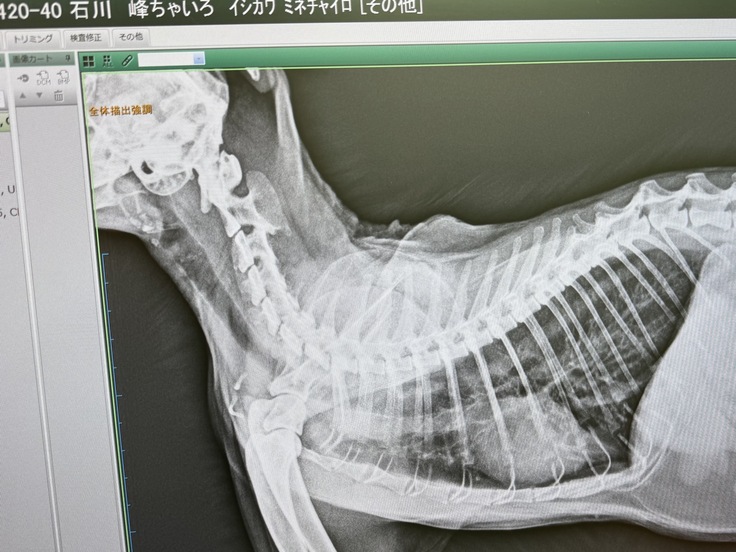

今回は、喘息のちゃいろちゃんのお話です。特に心配のお問い合わせが多かった子です。

峰さんとは、お電話で頻繁に連絡を取り合っておりましたので、喘息のちゃいろちゃんのことはよく聞いていました。

急変して病院に駆け込んだり、入院をしたお話をリアルタイムで相談され、容体について情報交換をしたりするなど、峰さんも最も気にかけておられた猫でした。

急いで当方のかかりつけ医に連れて行き、入院となりました。喘息に加えて気管支炎もあり、肺炎になり掛けていました。

翌日には呼吸状態は落ち着き安堵いたしましたが、喘息は想像以上に重く、強い薬は免疫力を下げてしまうため、改めて治療方針の提案をいただきました。